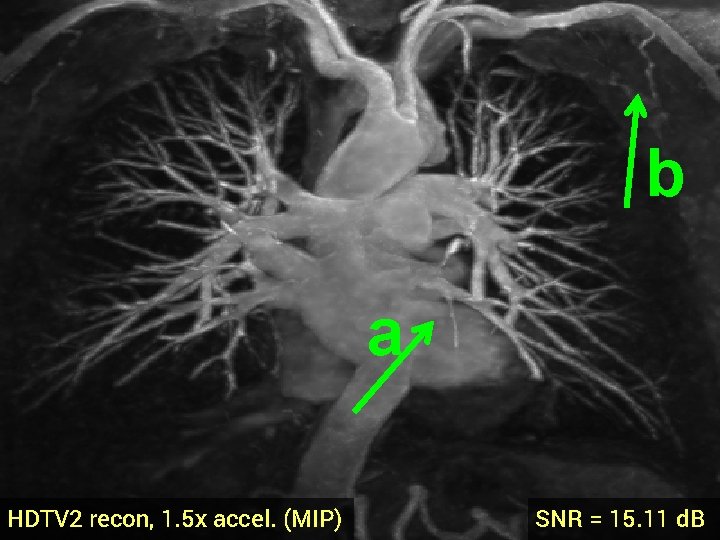

3 -D Compressed Sensing MRA § 512 x 76 voxel MRA dataset obtained from physiobank (see ref. [6]) § Simulated single coil acquisition § Retroactively undersampled at 1. 5 -fold acceleration § Random Gaussian sampling of k-space § 5 d. B additive Gaussian noise § Optimized regularization parameter MIP of original MRA dataset

b a TV recon, 1. 5 x accel. (MIP) SNR = 14. 53 d. B

b a HDTV 2 recon, 1. 5 x accel. (MIP) SNR = 15. 11 d. B

3 -D Quantitative Results Table 3: 3 -D Comparisons. SNR (in d. B) of recovered images with optimal reg. param. Denoising Cell 1 Cell 2 Deblurring Cell 1 CS-MRI Cell 2 Cell 3 Angio, acc=5 Angio, acc=1. 5 Cardiac TV 17. 12 16. 25 19. 02 16. 43 14. 50 13. 87 14. 53 18. 37 HDTV 2 17. 25 16. 70 19. 15 16. 60 14. 87 14. 23 15. 11 18. 56 HDTV 3 17. 68 17. 14 19. 73 17. 43 15. 23 14. 01 14. 70 18. 50 § HDTV outperforms TV in all experiments § HDTV 3 better for denoising and deblurring § HDTV 2 better for CS-MRI